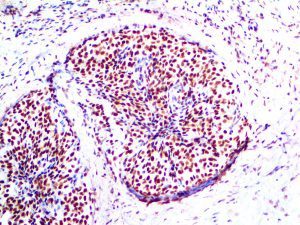

It is the ICU physician who is most likely to witness one of the deadliest manifestations of the abnormal immunological response, the cytokine storm syndrome (CSS). This response is also referred to by some as the cytokine release syndrome (CRS). CSS is characterized by continuous activation and expansion of macrophage and lymphocyte populations, which secrete large amounts of cytokines, causing the cytokine storm. This massive cytokine release is akin to hemophagocytic lymphohistiocytosis (HLH) disease, a syndrome characterized by initial unchecked and persistent activation of cytotoxic T lymphocytes and NK cells.

Clinical and laboratory manifestations of HLH include fever, enlarged liver and/or spleen, neurologic dysfunction, coagulopathy, liver dysfunction, cytopenias (i.e., low levels of erythrocytes, leukocytes, and/or platelets), hypertriglyceridemia, hyperferritinemia, hemophagocytosis, and eventually diminished NK cell activity as the immune system becomes progressively paralyzed. HLH can be familial (primary HLH) or secondary to another disease process (sHLH), such as rheumatic disease, in which it is referred to as macrophage activation syndrome (MAS, characterized by elevated ferritin).